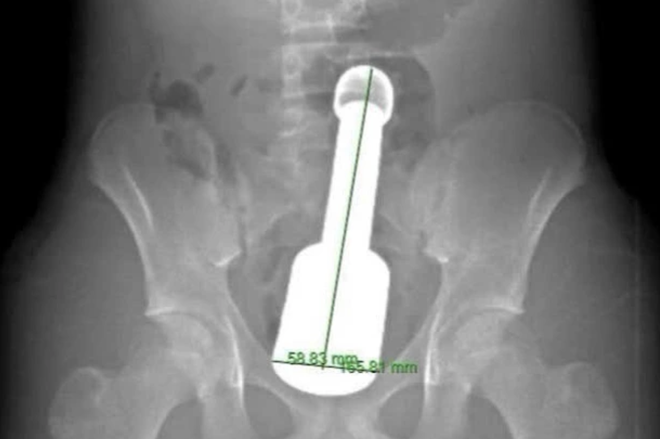

Hình ảnh chụp X-quang và dị vật được lấy ra khỏi hậu môn của bệnh nhân – Ảnh: BVCC

Bệnh nhân nhập viện trong tình trạng đau tức dữ dội vùng hạ vị. Kết quả chẩn đoán hình ảnh cho thấy một dị vật kim loại lớn mắc kẹt sâu trong trực tràng, gây chèn ép các cơ quan vùng chậu. Đây là tình huống nguy hiểm, dễ dẫn đến biến chứng nặng nếu không xử trí kịp thời.

Dị vật là một chiếc chày dài 18cm, đường kính 6cm. Thử thách lớn nhất đối với kíp mổ là dị vật quá to so với cơ thắt hậu môn của thiếu niên, đồng thời tạo ra “hiệu ứng chân không” khiến nó bị hút chặt vào lòng ruột.